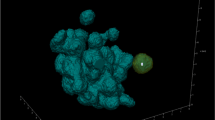

Visualisation

Three-dimensional volume representations of the reconstructed data sets and marked microsphere distributions were generated within the three-dimensional visualisation and measurement software package, Avizo 9.4 (Thermo Fisher Scientific). Renderings of the contrast agent were generated after segmentation via simple intensity thresholding of the phase retrieved reconstructed data.

For the full manual segmentation of one representative small tissue sample, the full phase retrieved reconstructed dataset was used for the input, then downsized with 2 × 2 × 2 binning. Inside the segmentation editor of Avizo each of the main observed constituent materials (adipose and muscle layers, contrast agent and air bubbles) were labelled with a combination of thresholding and magic wand tools. Manual tracing of the very low contrast fat-agarose interface was aided with the use of a Wacom graphics tablet and then selection interpolation. The corresponding unbinned binary map of the sample microsphere distribution was added and convolved with a gaussian shape function before separate volume rendering. Movies were created through use of the Avizo animation editor.

Three-dimensional reconstruction of tomographic images

Representative three-dimensional tomographic reconstructions, including volume renderings of microsphere and vehicle depot within porcine abdominal tissue are presented in Figs. 4 and 5.

Three-dimensional visualisation of microsphere and non-aqueous vehicle deposition within porcine abdominal tissue acquired using the module 1 setup. Volume renderings of the microspheres (yellow) and contrast agent (blue) are overlaid onto orthogonal reconstructions of injected tissue samples. In (A) the perspective camera view is shown, and in each of (B), (C) and (D) the top, longitudinal and transverse views are presented orthographically. The vertical height shown is 18 mm, and the cross-sectional diameter 42 mm.

Three-dimensional visualisation of microsphere and aqueous vehicle deposition within porcine abdominal tissue acquired using the module 1 setup. Volume renderings of microspheres (yellow) and contrast agent (blue) are overlaid onto orthogonal reconstructions of injected tissue samples. In (A) the perspective camera view is shown, and in each of (B), (C) and (D) the top, longitudinal and transverse views are presented orthographically. The vertical height is 18 mm, and the cross-sectional diameter 42 mm.

Data presented above demonstrate the relative localisation of injected microsphere suspensions within excised porcine abdominal tissue. Microspheres and vehicle co-localised in some regions of the depot, and the presence of microspheres along the needle track close to the centre of injection was evident for both formulations. However, some degree of separation in tissue distribution was observed between the contrast-labelled vehicle and microspheres. The vehicle in both cases migrated to site distal to the centre of the injection, whereas, the microspheres were predominantly localized in proximity to the centre of the injection.

A three-dimensional volume segmentation and rendering was also created for one representative sample, which is utilised in the graphical abstract and accompanying movie file. In Fig. 6, some stills are included which show the important features of the microsphere distribution within the porcine tissue.

Following image segmentation and removal of tissue and vehicle contribution (Fig. 6C-D), reconstructed microsphere depots show evidence of microsphere deposition along the needle tracks, with the bulk of microspheres located close to the centre of injection in a few clusters (depots). Some individual microspheres were located at distal sites within the excised tissue, consistent with the spread of injected (Fig. 6A-B).

Volume representations of aqueous and non-aqueous vehicle depositions demonstrate microsphere identification (in yellow) in the absence of contrast agent (Fig. 7A and B). These were two of the larger porcine tissue samples imaged with the LFV camera module. Therefore, this technique could be applied in the absence of contrast agent, in scenarios where the density difference between microspheres and vehicle was sufficient, circumventing any associated pitfalls, for example, the impact of labelling on formulation rheology.

Volume renderings of PLG microspheres in the absence of contrast agent (Fig. 7) were created to evaluate the feasibility for microsphere depot detection in ex vivo porcine tissue. The benefit of this representation is to examine the relative anatomical localization of drug-loaded microspheres within tissue through simultaneous visualization of tissue layers and deposited microspheres without the need for a contrast agent.